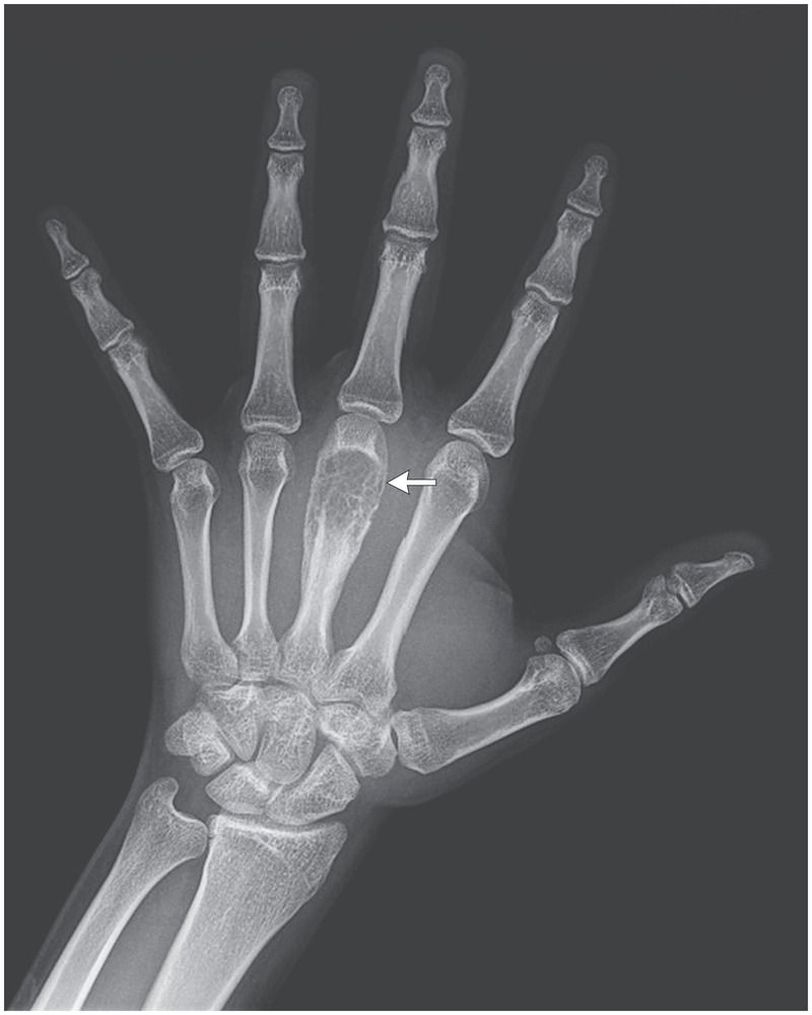

A 17-year-old boy was assessed because of a 2-month history of pain and swelling on the dorsal side of his left hand. The patient had visited Pakistan 6 months earlier. He had no known medical conditions and was not receiving medications. On physical examination, a hard and suppurative nodule was noted around the left third metacarpal. He had no fever or systemic symptoms, no lymphadenopathy, and no history of trauma. Results of serologic testing for the human immunodeficiency virus were negative. Radiography of the left hand revealed a slightly thinned cortex surrounding a lytic core with trabecular pieces on the third metacarpal bone (arrow); no periosteal reaction was seen. Chest radiography was normal. Ziehl–Neelsen staining of the exudate aspirated from the third metacarpal showed acid-fast bacilli, later identified as Mycobacterium tuberculosis in culture and a pan-sensitive isolate. For 2 months, he was treated with rifampin, isoniazid, ethambutol, and pyrazinamide, followed by 4 months of rifampin and isoniazid. He did not come to follow-up visits after completion of treatment because he had moved to Pakistan. Tuberculous dactylitis (also called spina ventosa) is a form of extrapulmonary M. tuberculosis infection, more common in children than in adults. Differential diagnoses include osteomyelitis, sarcoidosis, and bone neoplasms (e.g., enchondroma), which were considered in this case.